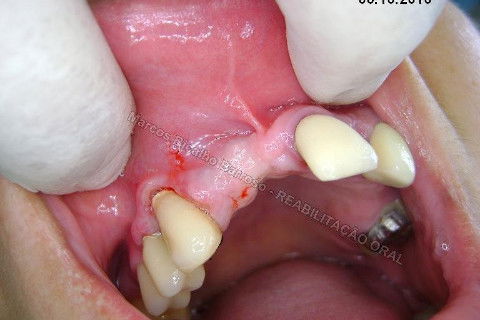

Reparem no corte...bonitinho mas fiquei com raiva depois. rsrsrs. Caramba, por que que eu tinha que tirar esta gengiva dali? Era só enrolar o excesso para a vestibular e conseguiria um bom aumento de volume gengival, o que ajudaria bastante na estética periimplantar. Mas tudo bem, vou fazer a cirurgia periodontal depois para corrigir isto sem cobrar da paciente, só de raiva. hehehe. Tem que rir para não chorar.

Aqui até que tudo bem, mas nos anteriores, não podia.